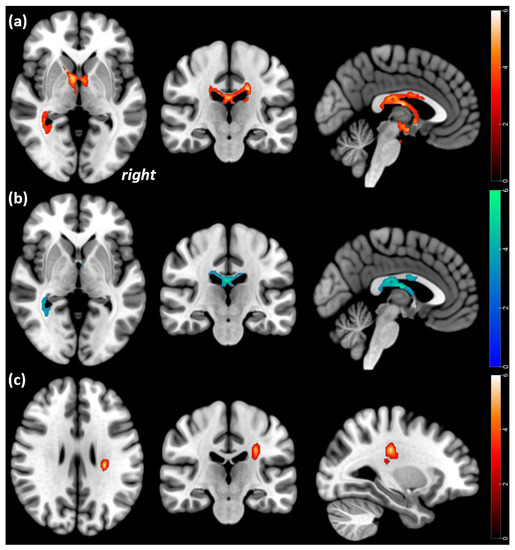

3.5. Cross-Sectional Comparisons of Patients with Attachment Trauma

| Significant regional differences in FA values in the 11 AN patients with attachment trauma compared to the 18 HC participants when corrected for BMI | |||||||

| Overlap of cluster region | kE | MNI coordinates | t value | p-value corrected at the cluster level (FWE) | Height Threshold | ||

| x | y | z | |||||

| Significant FA decreases in the 11 acute AN patients with attachment trauma compared to the 18 HC participants at Tp1 | |||||||

| Corpus callosum and cingulum bilaterally | 3035 | −10 14 16 | −40 −6 −18 | 12 40 40 | 5.2 | <0.001 | 0.01 |

| Significant FA decreases in the 11 AN patients with attachment trauma compared to the 18 HC participants at Tp2 | |||||||

| Corpus callosum and cingulum, left | 1393 | −12 | −40 | 12 | 4.4 | 0.005 | 0.01 |

| Corpus callosum and cingulum, right | 1312 | 14 | 12 | 38 | 3.8 | 0.007 | |